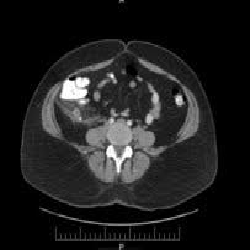

Figure 2:This image from August 2010 displays a slice of the CT scan of the abdomen with evidence of an inflamed appendiceal stump.

We report a second case of a 51 year old woman who presented to the ED in February 2010 with complaints of abdominal pain of 2 days duration. The patient underwent an uneventful laparoscopic removal of a ruptured appendix with irrigation of the peri-colic gutter. Patient was discharged on postoperative day 4. The patient presented to the ED in August 2010 complaining of nausea, vomiting, and pain similar to the appendicitis she had earlier that year. The patient presented with positive guarding and positive McBurney's sign. Laboratory studies showed a WBC count of 11,000/mcL and a CT scan suspicious for ruptured appendiceal stump. The laparoscopic procedure was performed and purulent fluid was drained from the pericolic gutter. Due to the inability to locate the appendiceal stump the procedure was converted to an open appendectomy. The inflamed appendiceal stump measured 3-4cm in length. Patient tolerated procedure well and was discharged on postoperative day 3.